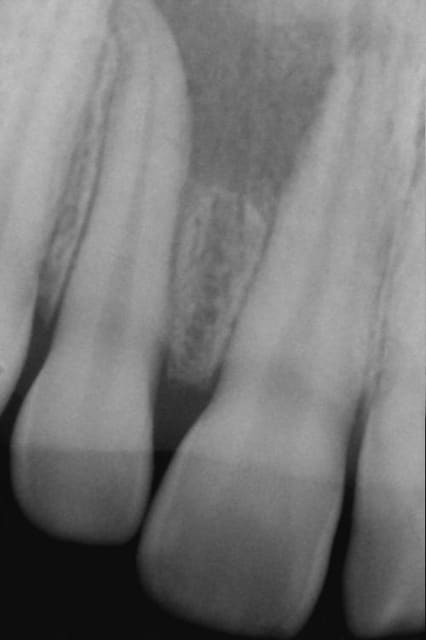

NB: ne pas chipoter svp sur l'appellation "kyste"

Kyste1 xpgssa - Eugenol

Kyste2 sef5wb - Eugenol

Repriseinit tk8kzi - Eugenol

Reprise4cx uandde - Eugenol